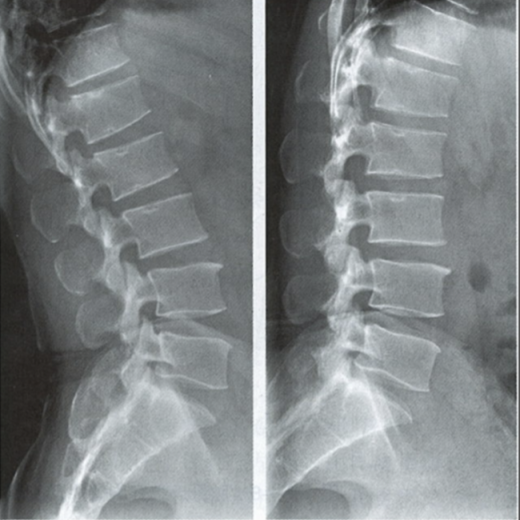

腰椎動(dòng)力位,也稱為過(guò)屈過(guò)伸位,可以理解為兩個(gè)極限體位下的側(cè)位片,腰椎動(dòng)力位通過(guò)做最大程度彎腰(過(guò)屈)和后仰(過(guò)伸)的動(dòng)作拍攝側(cè)位片,來(lái)觀察腰椎在極限活動(dòng)下的表現(xiàn)。如果說(shuō)腰椎側(cè)位片能靜態(tài)體現(xiàn)椎體的解剖學(xué)結(jié)構(gòu)、序列及生理曲度改變,那么腰椎動(dòng)力位則是評(píng)估腰椎動(dòng)態(tài)功能性的檢查。

腰椎過(guò)伸位:是指腰部盡可能向后伸展,以雙髖關(guān)節(jié)位支撐點(diǎn),運(yùn)動(dòng)前后骨盆位置無(wú)改變。腰椎過(guò)伸時(shí),向前的曲度大于生理曲度,上部向后傾斜。

腰椎過(guò)屈位:是指腰部盡可能向前彎曲,以雙側(cè)髖關(guān)節(jié)位支撐點(diǎn),運(yùn)動(dòng)前后骨盆位置無(wú)改變。腰椎過(guò)屈的表現(xiàn)位向前的曲度減小、變直,上部向前傾斜。

當(dāng)1度及以上的滑脫時(shí)才可以在普通腰椎側(cè)位上觀察到,而1度以下的滑脫或失穩(wěn)則在普通側(cè)位片上難以發(fā)現(xiàn),這時(shí)候就需要借助腰椎動(dòng)力位進(jìn)行診斷。

腰椎動(dòng)力位 左圖為過(guò)伸位、右圖為過(guò)屈位